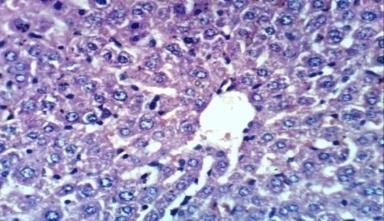

Fig. 4(a): Pancreas of normal control rats showed no histopathological changes (H & E X 400) |

Fig. 4(b): Pancreas of diabetic rat showed vacuolation of epithelial lining pancreatic acini (H & E X 400) |

Fig. 4(c): Pancreas of diabetic rats treated with crude extract of F. japonica showed no histopathological changes (H & E X 400) |

Fig. 4(d): Pancreas of diabetic rats treated with crude extract of F. japonica showed no histopathological changes (H & E X 400) |

The biochemical parameters were documented with histopathological finding which reveal hydropic degeneration of hepatocytes, sinusoidal leukocytosis and congestion of hepatoportal blood vessel in diabetic rats (photo 2b). While the kidney of diabetic rat showed atrophy of glomerular tuft and thickening of the parietal layer of Bowman’s capsule (photos 3b and 3c). Also, Pancreas of diabetic rat exhibited vacuolation of epithelial lining pancreatic acini (photo 4d). Treatment of diabetic rats with ethanol extracts of F. japonica demonstrated normal histological structure in kidney and pancreas architectures (photo 3c, 4c and 4c), while portal oedema was reported in liver (photo 2 c).